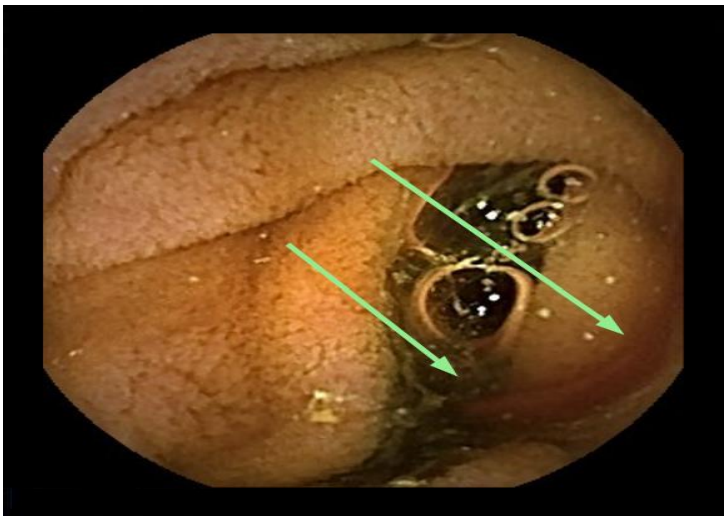

The patient was admitted with a severe IDA, confirmed by laboratory tests (Hb 4.3 g/dL, MCV 76 fl, ferritine 3 ng/ml), with no blood traces at rectal examination. Hemodynamical stability was maintained during all hospitalization; six blood transfusions was overall infused. Taking into account the previous investigations, a video capsule endoscopy (VCE) was performed showing minimal traces of red blood in the proximal small bowel lumen, without obvious mucosal lesions (Figure A). We decided to further investigate the small bowel with a per-oral device assisted enteroscopy (DAE), with identified a bulging with an adherent clot (Figure B) in the distal duodenum. The clot was gently washed with no signs of ongoing bleeding; its removal exposed a deep ulceration containing a yellowish structure behind (Figure C). An urgent angio-CT confirming the aorto-duodenal fistula (Fig. D) was performed and the patient was transferred to Vascular Surgery Department for surgical treatment.

A. Video capsule endoscopy: traces of red blood (green arrows) in the duodenal lumen without obvious mucosal lesions.

Taking into account the negative bidirectional endoscopies at time of admission, a VCE was performed, showing minimal traces of red blood in the proximal small bowel lumen. This finding, without evidence of obvious mucosal lesion, might be regarded as a minor non-relevant finding. However, bleeding from AEF typically occurs in two steps: a minor initial “herald” bleeding followed by a major bleeding event. Furthermore, in the proximal small bowel, VCE can depict bleeding signs but might miss even large lesions, because of its fast progression. Therefore, when even minor stigmata of recent bleeding (i.e. fresh blood in the lumen) are observed, further investigations, like per-oral enteroscopy, are mandatory. In addition, in such a case, all the efforts to minimize mucosal trauma (to prevent false positive findings) and to maximize small bowel surface inspection (to avoid false negative examinations) should be done. Therefore, this patient underwent per-oral DAE with CO2 insufflation and with a soft hood at the tip of the endoscope. These technical tricks allowed to carefully evaluate the small bowel mucosa and to safely inspect the ulcer base and to gently mobilize the clot, identifying the prosthesis wall (the yellowish mesh tubular structure showed in Figure B).